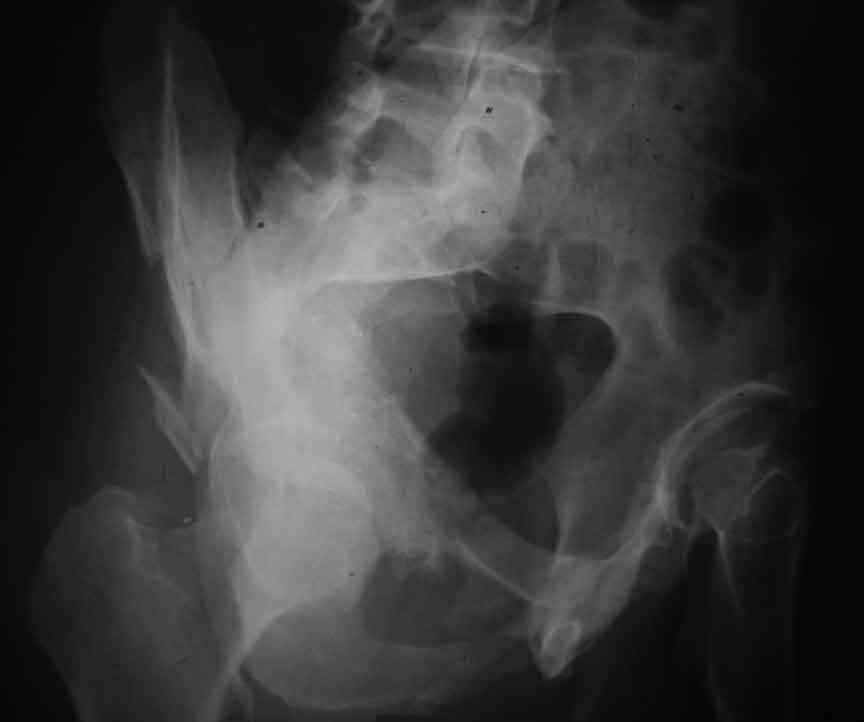

Dear Friends This is a 57 y old male.

Your input is welcome as to the classification of this fratcure, as well as the proposed management.

Dear Sir it looks quite difficult classify this fracture because the iliac view is not so clear.

In my opinion it is a column fracture because the obturator foramen is interrupted. There is a fracture of the posterior wall. If we assume the ap view as an iliac view it could be an anterior comun fracture plus posterior wall. It is difficult also to judge the head of the femur.

From the x rays it appears like a bicolumnar fracture with iliac extension (AO C1).